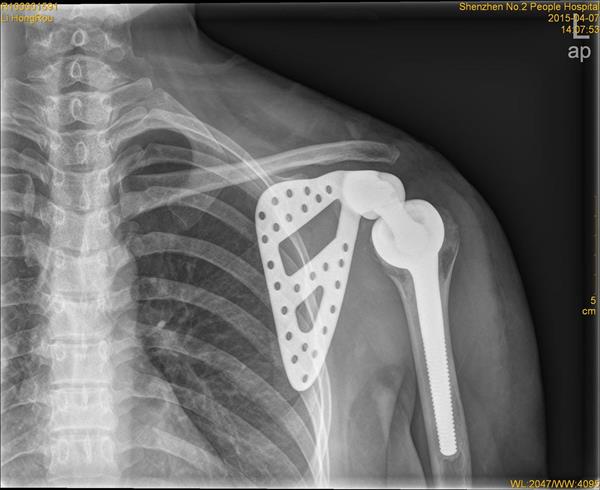

钛对未来考古学最重大的贡献在于其广泛的医学用途。1952 年,Per-Ingvar Brånemark 发现了“骨结合”现象,这标志着人类骨骼走向“赛博格化”时代的开启。钛合金植入物——如牙科螺钉、髋关节、骨板和心脏起搏器外壳——正式成为生物躯体的一部分,实际上正在制造混合的混合遗骸。

对于 5026 年的考古学家而言,一个微小的钛合金骨植入物的价值将远超骨骼本身,因为随着土壤的酸性侵蚀,骨骼可能会完全矿化甚至彻底消失。相反,钛不仅得以幸存,还将保存有关个体健康状况、其可获得的医疗水平以及社会经济地位等海量信息。

牙科植入物是人类遗骸中数量最为庞大的钛质工艺品。与主要使用汞合金或金冠进行传统填充不同,钛螺柱是被直接植入并固定在颌骨当中的,并成为了它本身的结构组成部分。

这种微小物体的庞大信息容量极其惊人:

- 技术溯源:通过研究其螺纹结构、连接形态及合金特性(例如 Ti-6Al-4V 或 Ti-Zr),未来科学家将能轻易辨认出具体的技术流派,甚至得出实施医疗干预的准确历史年代。

- 标记和数据库记录:依照现代 FDA(美国食品药品监督管理局)规定要求,各植入物表面必须被附上唯一的医疗器械标识(UDI)。这些普遍通过激光退火方式形成的独特微观刻文具有出色的耐磨及防腐性能。在软组织及骨骸全部降解殆尽后,这些细微记号依然存在,从而向掌握了修复后数字化数据的考古学家透露死者的姓名、出生年份及进行手术的具体国度。

- 阶层判定依据:钛合金修复系统在价格上一直相较于普遍替代手段显著偏高。能够拥有这些设备标志着所属特定的富裕社会地位及经济圈定。